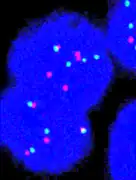

Fluorescence in situ hybridisation

FISH can be used to measure the number of copies of the gene which are present and is thought to be more reliable than immunohistochemistry.[47] It usually uses chromosome enumeration probe 17 (CEP17) to count the amount of chromosomes. Hence, the HER2/CEP17 ratio reflects any amplification of HER2 as compared to the number of chromosomes. The signals of 20 cells are usually counted.

-

This cell displays 2 signals of HER2 (red) and 3 signals of CEP17 (green) -

Two signals that are closer to each other than the signal diameter count as one. -

One of these signals is too faint, and is presumably debris. -

Cells with only one type of signal are excluded from the count. -

Overlapping cells are also excluded from the count. -

A yellow signal counts as one red and one green (which are overlapping)